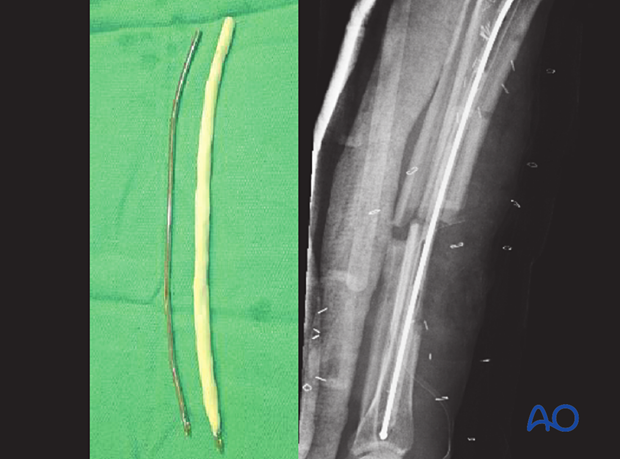

If the infection is late, or due to resistant organisms, external fixation may be preferable. An alternative is to temporarily place a reinforced, antibiotic-containing polymethylmethacrylate (PMMA) nail into the medullary canal. This is done after reaming out the infective membrane and undertaking a thorough lavage of the IM canal. Excision of any sinus track and sequestra must also be carried out.

An antibiotic-loaded PMMA nail is prepared by injecting liquid bone cement, pre-mixed with antibiotics (eg, tobramycin 1 g per cement batch) into both ends of an appropriately sized chest tube which is vented in the middle to allow complete filling. A small-diameter flexible rod (eg, nailing guide wire) is inserted before the cement hardens. The chest tube is then cut off.

The “nail” can be left in situ until the fracture has healed, or until the infection is under control, and then replaced with a solid metallic nail. A solid nail is used rather than a hollow nail because a hollow nail may become a hiding place for bacteria.

A conventional nail that is covered with antibiotic bone cement can also be used. The benefit of this type of nail is that the proximal and distal ends can be affixed with interlocking screws, allowing control of length, alignment, and rotation. In addition, weight bearing can be allowed.